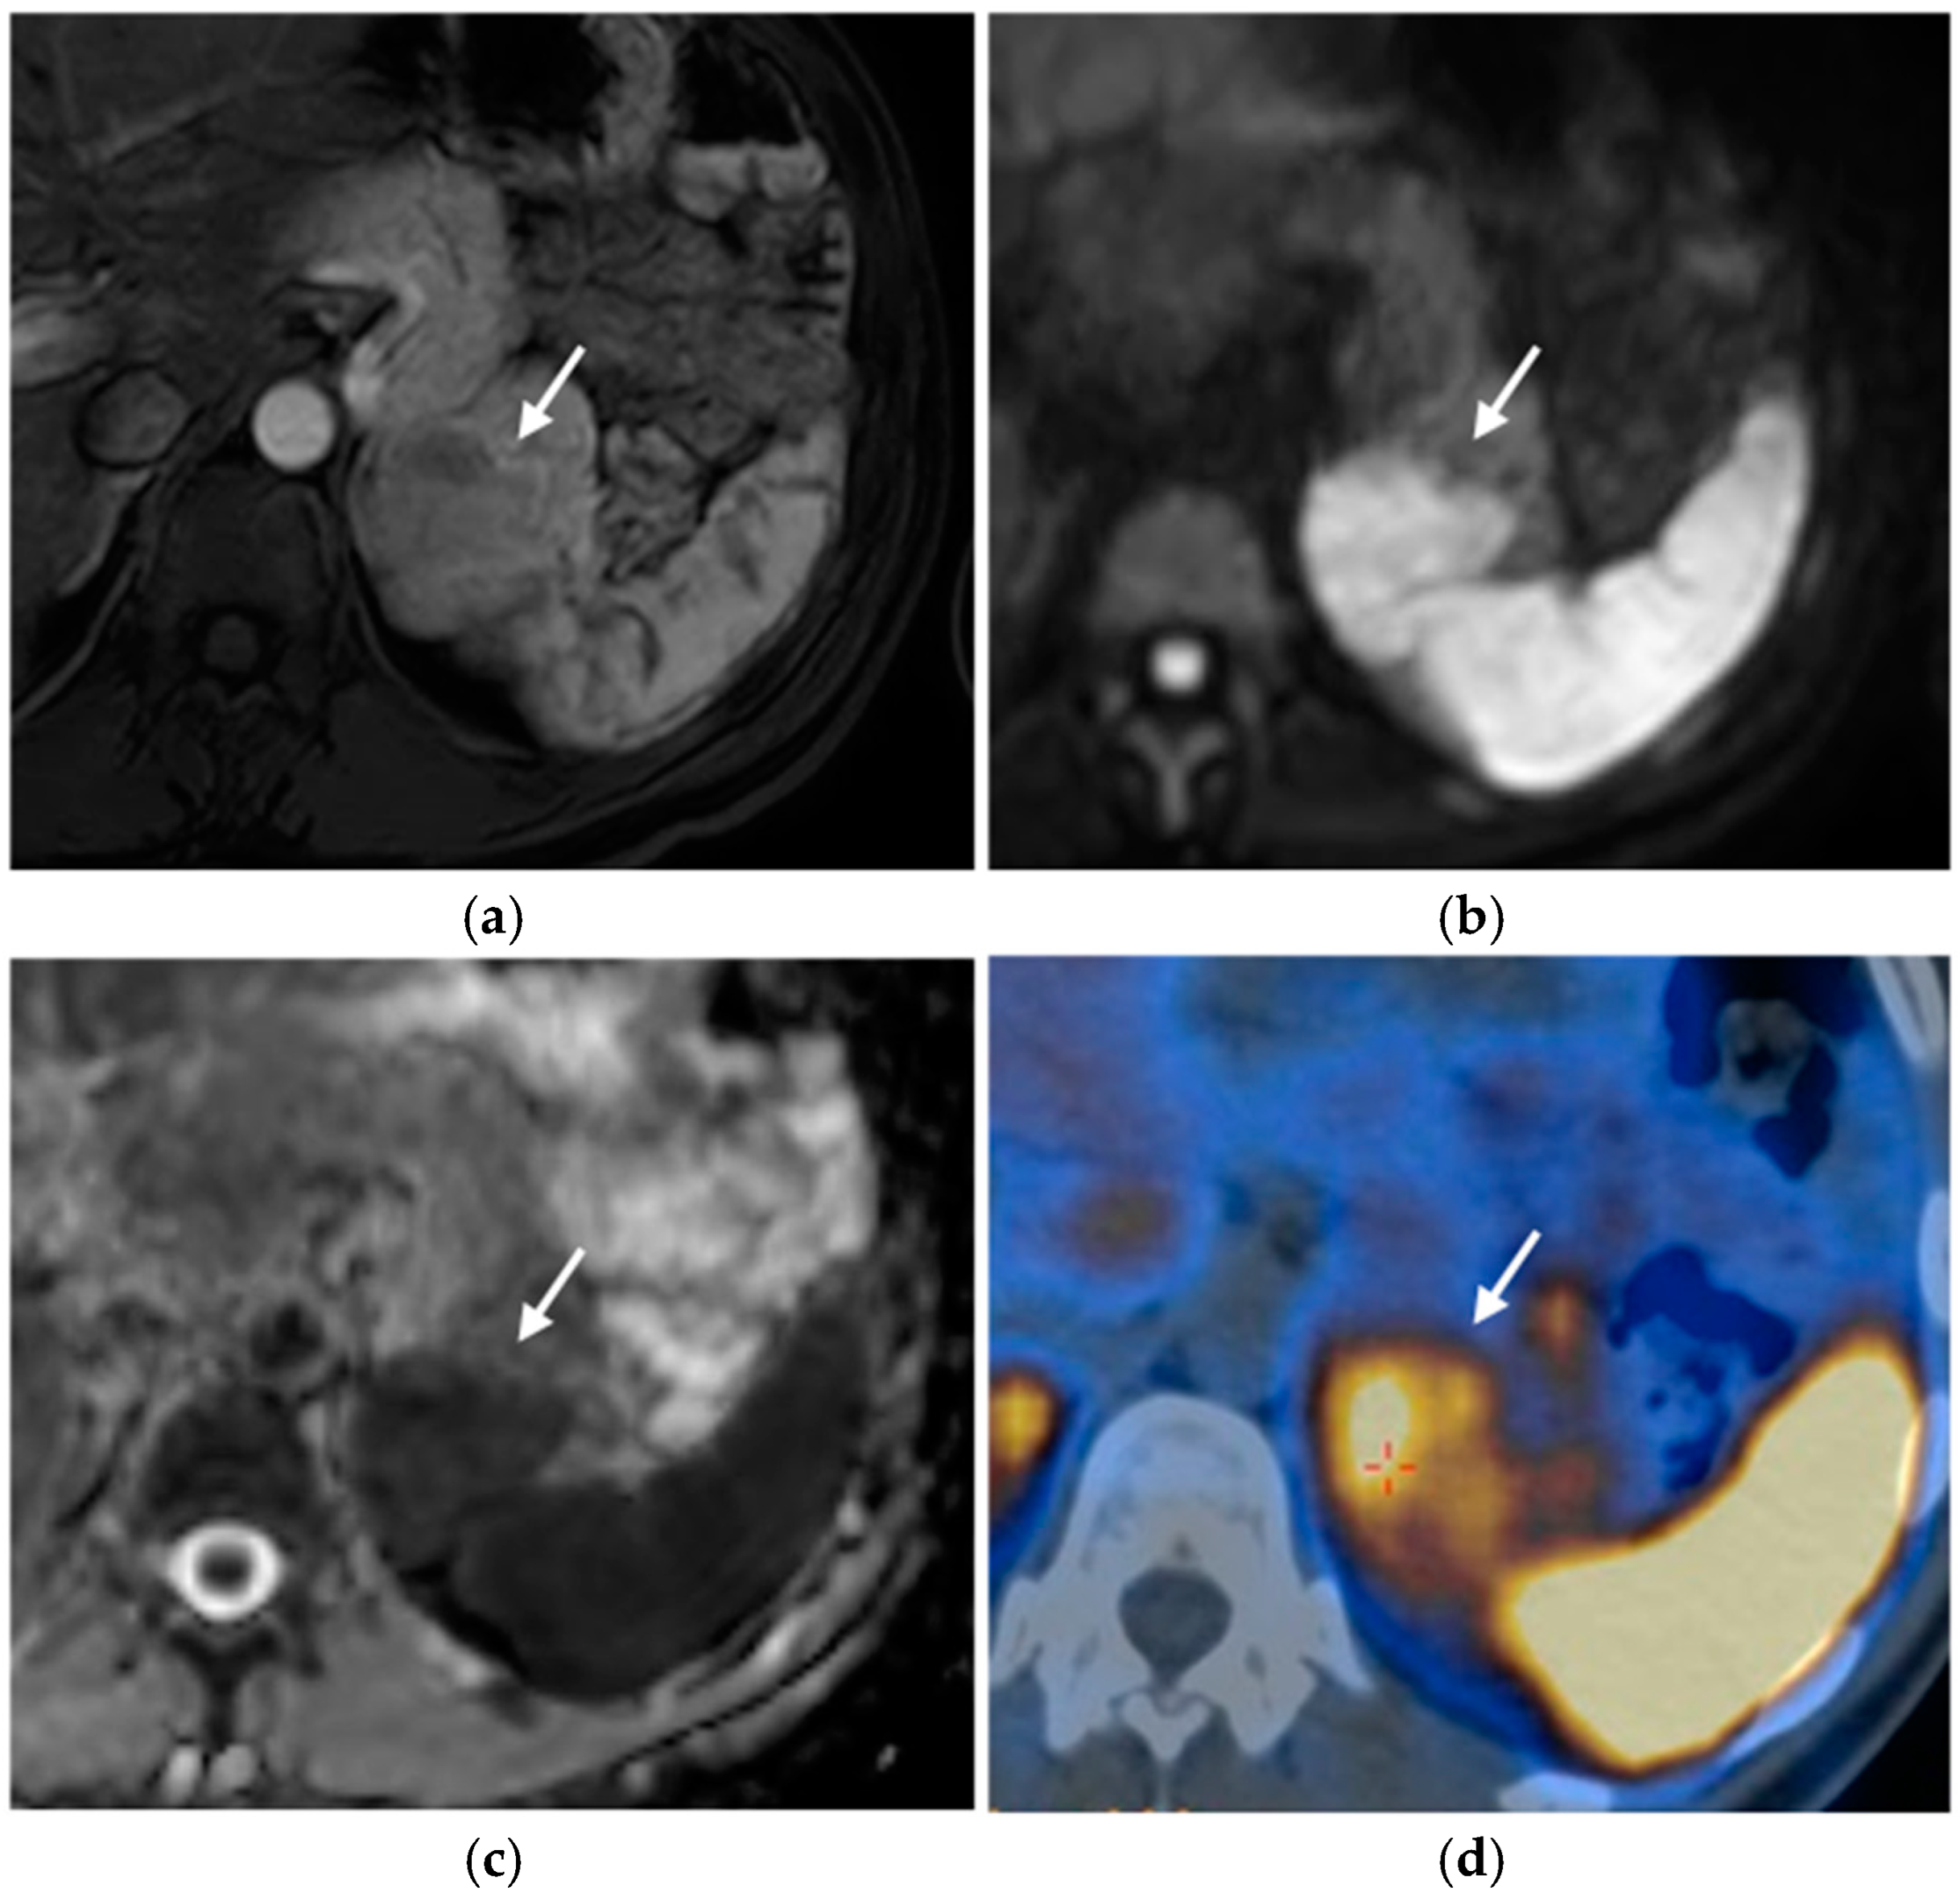

MRI

- Chaudhary, V.; Bano, S. Imaging of the pituitary: Recent advances. Indian J. Endocrinol. Metab. 2011, 15, 216. [Google Scholar] [CrossRef]

- Gruppetta, M. A current perspective of pituitary adenoma MRI characteristics: A review. Expert. Rev. Endocrinol. Metab. 2022, 17, 499–511. [Google Scholar] [CrossRef] [PubMed]